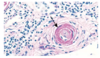

What pathology is shown in the provided image?

Describe the features of the vessel & in what conditions this pathology occurs.

Hyaline arteriolosclerosis

Thickened arteriolar wall with increased plasma protein deposition and narrowed luman

very homogenously pink

Congo red stain will be negative

occurs in chronic hypertension & diabetes mellitus